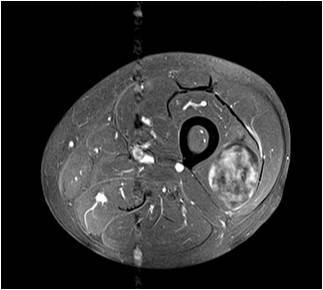

Gallery of Unlabled Radiographs from Lecture (Dr. French) - 2020

Click a thumbnail to enter the gallery display. Click the file name link at the bottom left of the gallery display to view the image at high resolution.